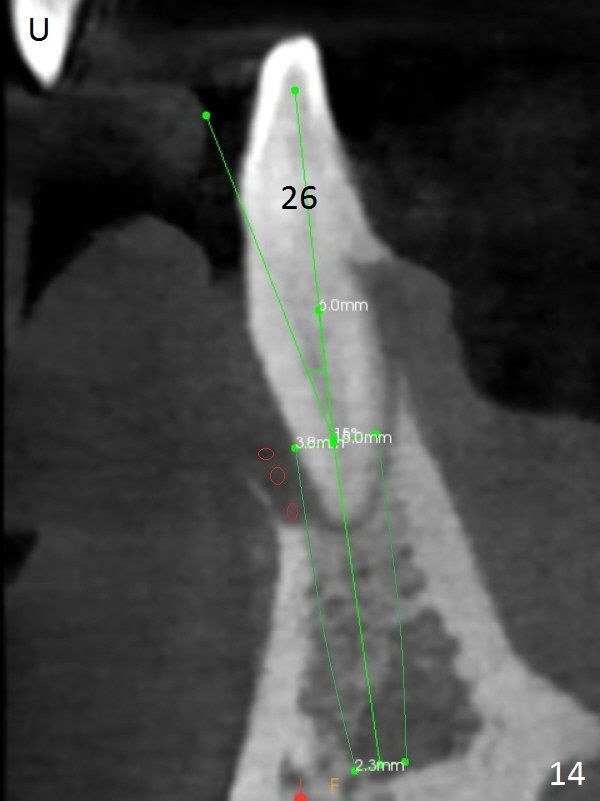

Class II Division II malocclusion (Fig.2,6) will make it difficult to restore #23-26 implant-supported FPD. Although the teeth #7-10 may need to be replaced later (Fig.7,8), enameloplasty will be conducted for #7-10 (Fig.9 white area; Fig.12 black circles (gross reduction)) prior to #23-26 extraction and implant placement (Fig.10). To be flexible in restoration (angulation) and possible future hybrid denture, 2-piece narrow implants will be placed (3.0 or 3.3 mm) instead of 1-piece ones. In fact CBCT shows that the narrowest regular implant (3.8 mm) can be placed in the lower anterior region (Fig.13-15).